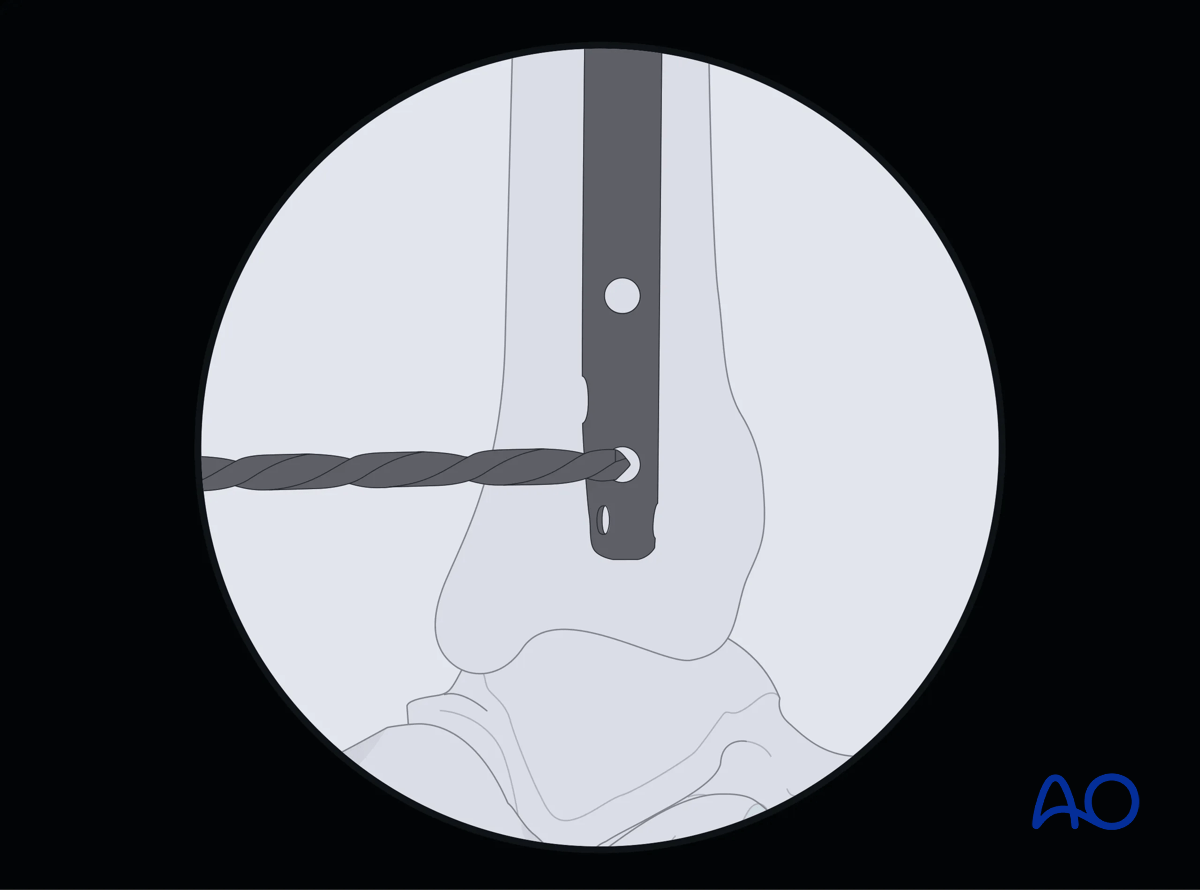

The central ray of the fluoroscope must pass through the locking hole so that its image is perfectly round and centered on the display screen. This confirms that the central ray is perpendicular to the nail.

Suprapatellar intramedullary nailing, Distal interlocking with fluoroscopic guidance

Drill tip positioning

The drill tip is positioned over the center of the locking hole.

The drill tip must be aligned with the fluoroscopic central ray. The drill is then advanced through the near tibial cortex, the locking hole in the nail, and the far tibial cortex. Its position is confirmed radiographically. If correct, screw length is measured, the appropriate screw is inserted, and its proper placement is confirmed radiographically.